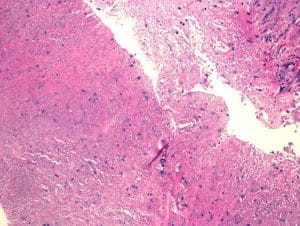

Figure 3: Hematoxylin and eosin stain of residual benign lung alveolar tissue and surrounding fibrous stroma with chronic inflammation and extensive necrosis with no evidence of malignancy seen (10x, scale bar 500 lm)

Figure 4: Extensive necrosis with no residual epithelium in this field. (5x, scale bar 500 lm)